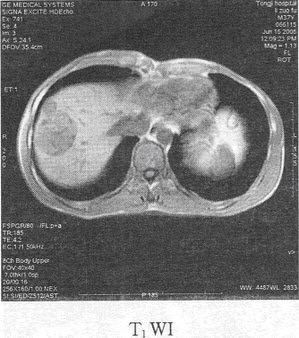

患者男,54岁。体检发现肝脏占位,MR图像如下,最有可能的诊断是()

A:肝肉瘤

B:肝腺瘤

C:肝血管瘤

D:肝癌

E:肝再生结节